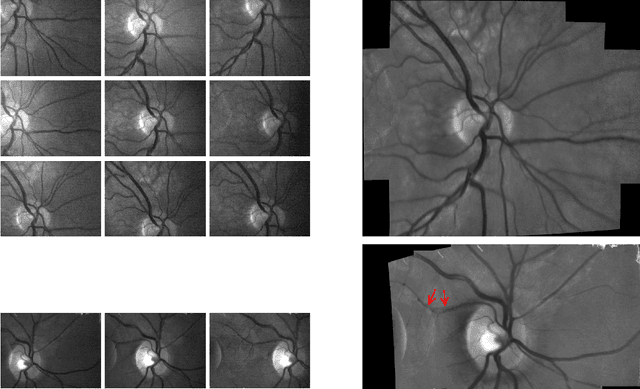

Abstract:The acquisition of high-resolution retinal fundus images with a large field of view (FOV) is challenging due to technological, physiological and economic reasons. This paper proposes a fully automatic framework to reconstruct retinal images of high spatial resolution and increased FOV from multiple low-resolution images captured with non-mydriatic, mobile and video-capable but low-cost cameras. Within the scope of one examination, we scan different regions on the retina by exploiting eye motion conducted by a patient guidance. Appropriate views for our mosaicing method are selected based on optic disk tracking to trace eye movements. For each view, one super-resolved image is reconstructed by fusion of multiple video frames. Finally, all super-resolved views are registered to a common reference using a novel polynomial registration scheme and combined by means of image mosaicing. We evaluated our framework for a mobile and low-cost video fundus camera. In our experiments, we reconstructed retinal images of up to 30{\deg} FOV from 10 complementary views of 15{\deg} FOV. An evaluation of the mosaics by human experts as well as a quantitative comparison to conventional color fundus images encourage the clinical usability of our framework.